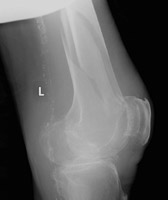

- Click on the image for a larger versionAAP radiograph of the distal femur. This demonstrates a comminuted, overriding fracture of the distal femur. There is profound osteopenia.